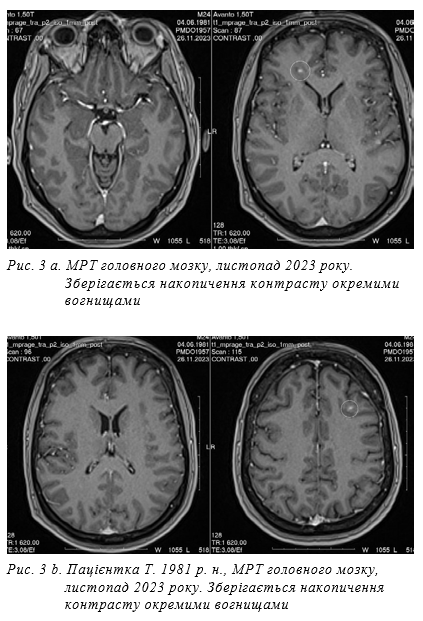

Після цього біль зник, рана загоїлась. До стоматолога по допомогу не зверталась. Пацієнтка була екстрено спрямована до стоматолога, хірурга. Вогнище запалення було дреновано. З рани виділено за результатами бактеріологічного дослідження — Streptococcus mitis 106. Подальша антибактеріальна терапія була продов- жена з урахуванням чутливості виділеного збудника до антибактеріальних препаратів. Пацієнтка була виписана у задовільному стані: в свідомості, збільшилась сила в правих кінцівках на 1 бал; розширився об’єм рухів, але турбував періодичний головний біль. Діагноз при виписці: множинні абсцеси головного мозку, вторинний гнійний менінгоенцефаліт одонтогеної етіології з розвитком набряку-набухання головного мозку, гіпертензійно-гідроцефального синдрому, бульбарних розладів, правобічного прозопарезу, помірного правобічного геміпарезу, вестибуло- кохлеарних порушень, стійкого цереброастенічного синдрому. Цукровий діабет II типу, стадія субкомпенсації. Пародонтальний абсцес. Рекомендовано подальше підтримуюче лікування за місцем проживання, спостереження сімейного лікаря, невролога, інфекціоніста, ендокринолога, нейрохірурга, хірурга-стоматолога. Призначена консолідуюча антибактеріальна терапія: моксифлоксацин 400 мг на добу + лінезолід 600 мг 1 раз на добу + флуконазол 200 мг на добу до 1 міс. Після виписки пацієнтка залишилась під спостереженням з регулярним контролем лабораторних показників, МРТ головного мозку. Впродовж 2 років пацієнтка поступово фізично та психологічно відновлювалась, працювала за спеціальністю, рецидивів зафіксовано не було. За даними контрольного МРТ головного мозку через 4 міс. після початку хвороби (рис. 3 a, b, c): 15.10.23 МРТ виконані T2WI, T2_spc_flair_iso, T1_ mpr, DWI, SWI томограми головного мозку в аксіальній, корональній та сагітальній проєкціях, T1_mpr + C з подальшою мультипланарною реконструкцією. МР-картина множинного вогнищевого ураження супра- та інфратенторіальних відділів головного мозку, що за МР- характеристиками може більш ймовірно відповідати множинним внутрішньомозковим абсцесам (бактеріальної/ фунгальної/специфічної етіології?). Порівняно з попередньою МРТ від 25.08.2023 р. визначається позитивна динаміка у вигляді зменшення розмірів вогнищ та зон перифокального набряку (див. опис), деконфігурація вогнищ, зникнення капсул вогнищ (ймовірно, відображає стадійність резорбції абсцесів).

Кількість вогнищ попередня, появи нових вогнищ не визначається. Супутня знахідка: виявлене округле вогнище в зоні верхньої щелепи праворуч (верхній зубний ряд праворуч) при попередній МРТ наразі чітко не візуалізується. Визначається потовщення слизової оболонки верхньої щелепи праворуч до 6,8 мм. Контрольне МР обстеження через 2 роки показало позитивну динаміку, регрес вогнищевих змін головного мозку (рис. 4 а, b). 7.06.2025 МР виконані T2WI, DWI, SWI, T2_spc_ dark-fluid_iso, T1 MP-RAGE_iso, T1 MP- RAGE_iso + C сагітальні, корональні та аксіальні томограми головного мозку з подальшою мультипланарною реконструкцією. МР-картина множинного вогнищевого ураження супра- та інфратенторіальних відділів головного мозку, що за МР-характеристиками може більш ймовірно відповідати множинним внутрішньомозковим абсцесам в стадії регресу. Порівняно з попередньою МРТ від 26.01.2025 р. відсутнє накопичення контрасту окремих вогнищ, в решті